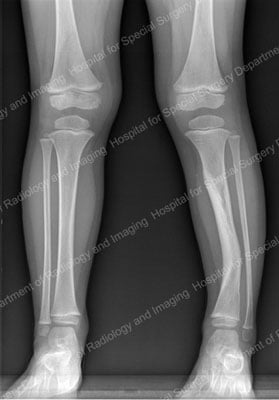

Unlike the benign bowing of the legs that is not uncommon in healthy young children, the bowing of the tibia that is associated with neurofibromatosis has a distinctive orientation − an anterolateral bow (see figure below). This may lead to fracture and tibial pseudarthrosis (non-union). In such cases, surgical intervention is recommended. This is especially the case if the condition affects a child’s gait or ability to walk. Surgery can restore or improve walking function.

Anteroposterior (front-to-back) X-ray showing an anterolateral bowing in the tibia of a young patient